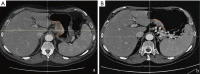

Figures